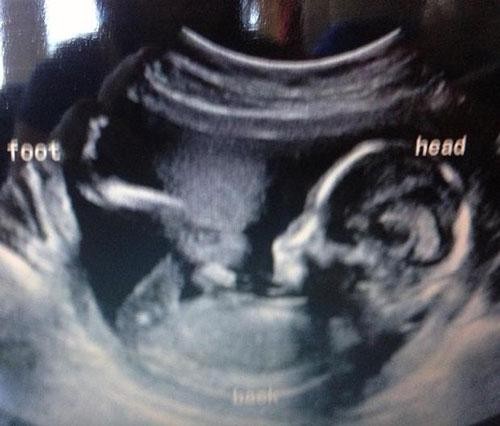

İşte bebek ultrasonlarında çekilen ve bazı anne babalara mini kalp krizi geçirten bebek fotoğrafları!